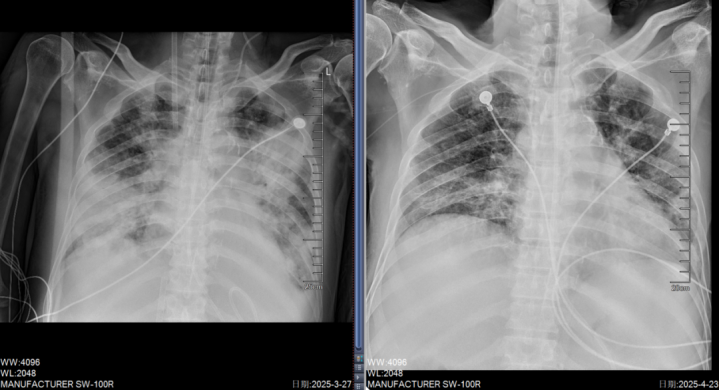

虽经积极抗病毒、抗感染治疗,患者病情仍急剧恶化,很快出现神志转差、血氧饱和度急剧下降等症状,诊断为重症肺炎合并呼吸衰竭,紧急转入ICU监护治疗。

进入ICU时,张先生已并发重度急性呼吸窘迫综合征(ARDS)、感染性休克,气道内积聚大量脓痰,二氧化碳潴留明显,还出现了呼吸性酸中毒,多脏器功能衰竭。更棘手的是,患者有肝硬化病史,这意味着若采用ECMO(体外膜肺氧合)辅助治疗,极易引发出凝血功能紊乱等严重并发症。

ECMO启动后,医护团队24小时全程守护,开云密切监测患者的生命体征、凝血功能、感染指标等,根据病情变化及时调整治疗方案。随着治疗的逐步推进,患者的感染得到有效控制,呼吸功能逐渐恢复。

在ECMO支持11天后,成功撤机;又经7天精心治疗与呼吸康复,张先生神志转清,顺利拔除气管插管,转回普通病房继续治疗,最终康复出院。